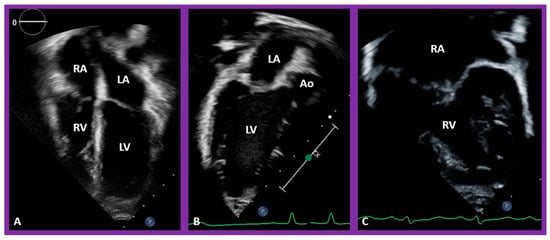

5.3. Are There Two Ventricles or One? If Two, Where Are the Ventricles Located in Relation to Each Other?

In theory, patients with cardiac malposition may have one (single) or two ventricles. The distinction between one and two ventricles is feasible by echocardiography (Figure 30) and angiography (Figure 31 and Figure 32).

Figure 30. Selected pictures from apical four-chamber echo views of two children, the first (A), who has two ventricles, and the second (B), who has one (single) ventricle (SV). The left atrium (LA), left ventricle (LV), right atrium (RA), and right ventricle (RV) are labeled. Reproduced from reference [4].

5.4. What Is the Status of Atrioventricular Connections?

After the visceroatrial situs and the ventricular locations are defined, the relationship between atria and ventricles should be assessed. These relationships are: concordant, with the RA emptying into the RV and the LA emptying into the LV (Figure 30A), and discordant, with the RA emptying into the morphologic LV and the LA emptying into the morphologic RV (Figure 39). Other AV connection abnormalities are: both the right and left atria emptying into a single ventricle (double-inlet left ventricle (Figure 30B)), both atria emptying into both ventricles via one common AV valve in the form of AV septal defect (Figure 42), a common atrium emptying into a single ventricle via a single AV valve (the so-called cor biloculare) (Figure 43), a common atrium emptying into inverted ventricles via a single AV valve (Figure 44) and atresia of either tricuspid or mitral valve (Figure 45). In addition, straddling or overriding of the AV valve over the ventricular septum may also occur. Such abnormalities may be defined by methodical echocardiographic imaging with the rare need for MRI, CT, and angiographic studies.